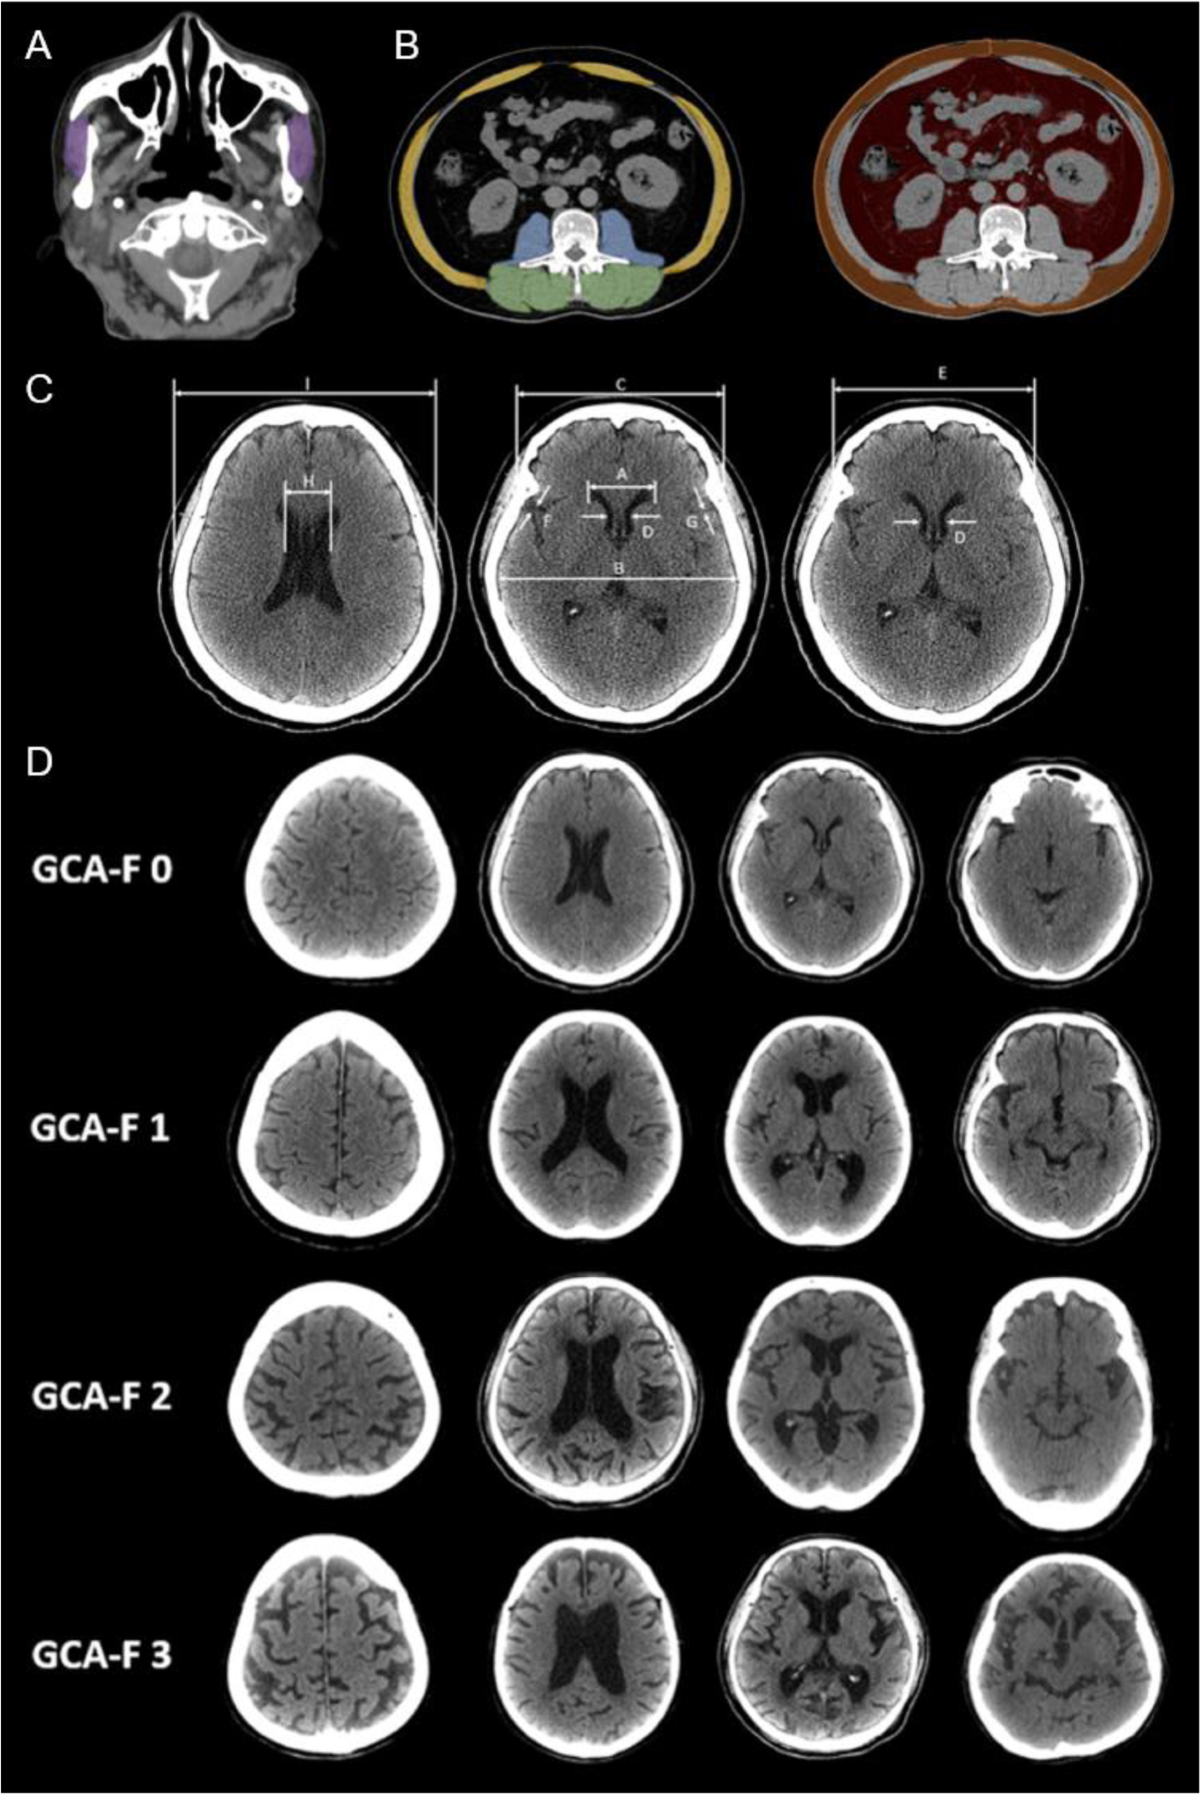

*Radiological assessment of dementia: the Italian inter-society *

*Brain CT can predict low lean mass in the elderly with cognitive *